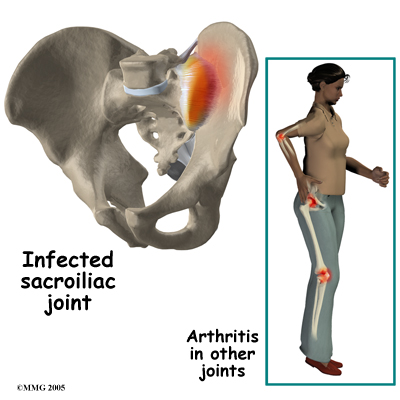

The SI joint is a synovial joint, similar to most other joints such as the knee, hip and shoulder. Due to it being a synovial joint, different types of arthritis that can affect the other joints of the body can also affect the sacroiliac joint. This includes rheumatic conditions such as rheumatic arthritis, gout and psoriasis. The SI joint can be infected when bacteria that travel in the blood settle in the joint causing a condition called septic arthritis. This is perhaps the most worrisome possible cause of SI joint pain and may well require surgery to drain the infection.

Most commonly the pain from an SI joint dysfunction is either directly over the SI joint itself or may radiate pain lower down into the buttocks. The pain may affect one side or both SI joints. Most times the pain from an irritable SI joint remains well above the knee, but in a few cases it can radiate down the leg all the way to the foot and may be confused with a herniated disc of the lumbar spine. The pain may also radiate into the groin area. People often feel muscle spasm or tightness in one or both of their buttocks muscles when the SI joint is affected.

Most commonly the pain from an SI joint dysfunction is either directly over the SI joint itself or may radiate pain lower down into the buttocks. The pain may affect one side or both SI joints. Most times the pain from an irritable SI joint remains well above the knee, but in a few cases it can radiate down the leg all the way to the foot and may be confused with a herniated disc of the lumbar spine. The pain may also radiate into the groin area. People often feel muscle spasm or tightness in one or both of their buttocks muscles when the SI joint is affected.

Most commonly the pain from an SI joint dysfunction is either directly over the SI joint itself or may radiate pain lower down into the buttocks. The pain may affect one side or both SI joints. Most times the pain from an irritable SI joint remains well above the knee, but in a few cases it can radiate down the leg all the way to the foot and may be confused with a herniated disc of the lumbar spine. The pain may also radiate into the groin area. People often feel muscle spasm or tightness in one or both of their buttocks muscles when the SI joint is affected.

Most commonly the pain from an SI joint dysfunction is either directly over the SI joint itself or may radiate pain lower down into the buttocks. The pain may affect one side or both SI joints. Most times the pain from an irritable SI joint remains well above the knee, but in a few cases it can radiate down the leg all the way to the foot and may be confused with a herniated disc of the lumbar spine. The pain may also radiate into the groin area. People often feel muscle spasm or tightness in one or both of their buttocks muscles when the SI joint is affected.